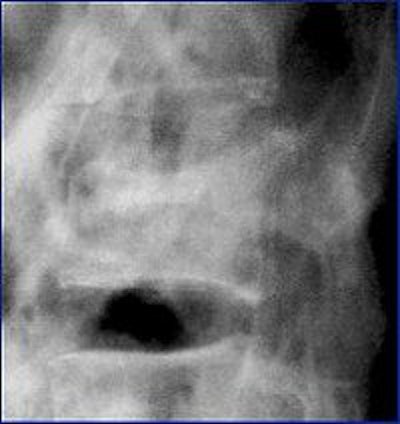

Whichever model is chosen, Cinnamon advised paying attention to the inverse relationship of contrast and spatial resolution, using the following case as an example (images F-G).

| Image F |

"On the 2.5-mm slice, you can see the occipital condyle fracture. If (you) go down to the 0.5-mm slice, you can see the fracture just as well -- maybe it looks a little sharper. But you can still identify the fracture on the thicker slice. The value for this is on the coronal and sagittal reformatted images from the 2.5-mm axials. There's a tremendous amount of stair-step artifacts. On the 0.5-mm images, you've eliminated the stair-step artifact because your spatial resolution is so good."